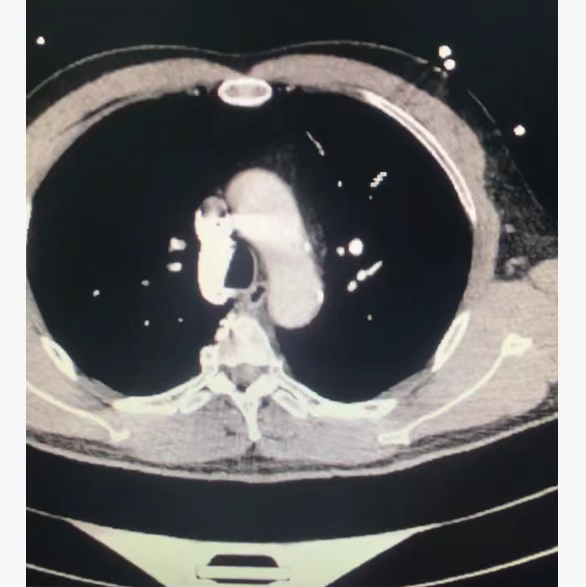

肺栓塞被称为“沉默的杀手”,大面积栓塞可在短时间内引发急性右心衰竭、休克甚至猝死。急诊科立即启动绿色通道,急查CT肺动脉造影(CTA),结果证实:患者肺动脉主干及主要分支被血栓完全阻塞,确诊为大面积肺栓塞,病情极度危急!

溶栓药物(重组组织型纤溶酶原激活剂)缓缓注入患者体内。ICU团队彻夜守护,每15分钟监测一次生命体征:

• 溶栓前:血氧饱和度88%-89%(正常>95%),血压72/45mmHg(休克临界值),呼吸急促至30次/分以上,意识模糊;

• 溶栓半小时后:血氧饱和度升至92%,血压回升至90/60mmHg;

• 溶栓1小时后:血氧饱和度稳定在98%-99%,血压升至112/78mmHg,呼吸频率降至22次/分,意识逐渐清醒。